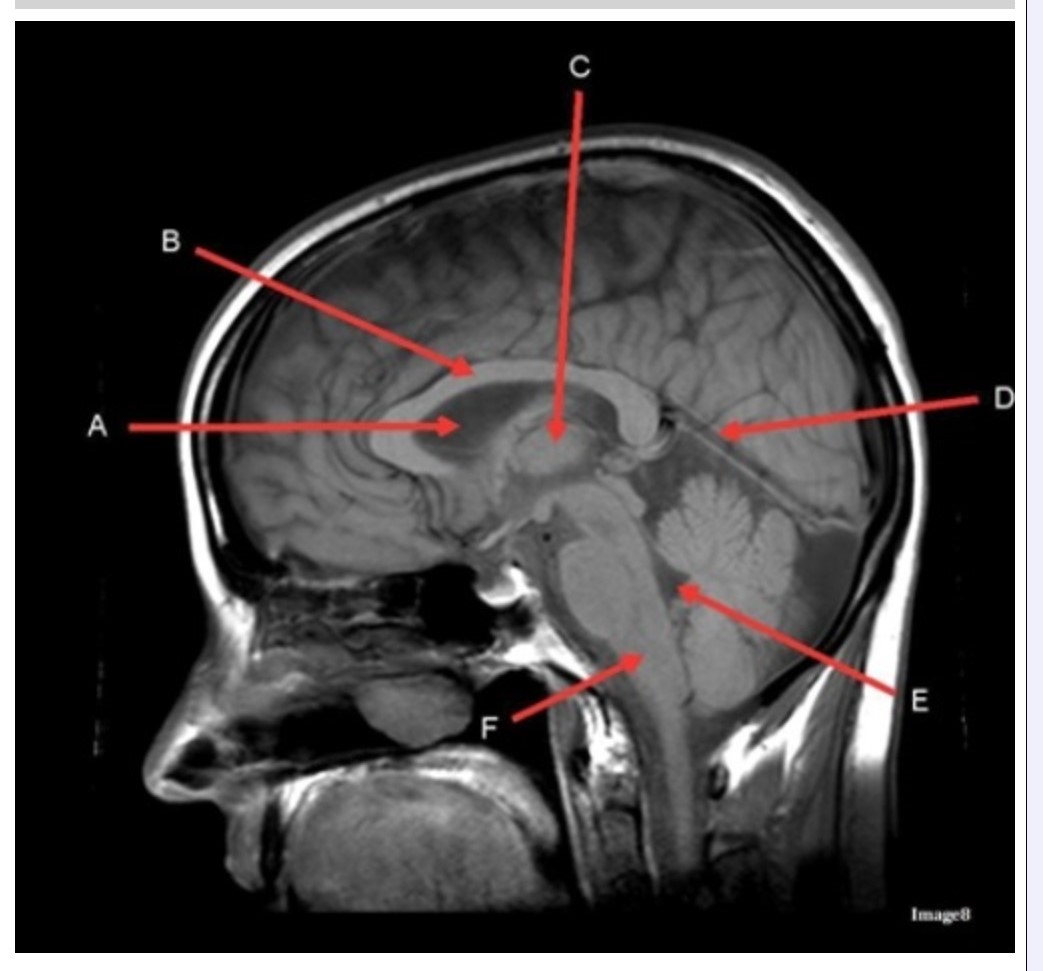

Letter C in Image 8 is pointing to:

A. Tentorium

B. Corpus callosum

C. Thalamus

D. Fourth ventricle

E. Medulla oblongata

Letter F in Image 8 is pointing to:

A. Tentorium

B. Cerebellum

C. Thalamus

D. Fourth ventricle

E. Medulla oblongata

Letter A in Image 8 is pointing to:

A. Tentorium

B. Corpus callosum

C. Hypothalamus

D. Fourth ventricle

E. Lateral Ventricle

Letter E in Image 8 is pointing to:

A. Tentorium

B. Cerebellum

C. Thalamus

D. Fourth ventricle

E. Medulla oblongata

Letter B in Image 8 is pointing to:

A. Tentorium

B. Corpus callosum

C. Hypothalamus

D. Fourth ventricle

E. Medulla oblongata

Letter D in Image 8 is pointing to:

A. Tentorium

B. Cerebellum

C. Thalamus

D. Fourth ventricle

E. Medulla oblongata

Image 8 is an example of a _______ weighted sequence acquired in the _______ scan plane.

A. T1; Axial

B. T1; Sagittal

C. T2; Axial

D. T2; Sagittal